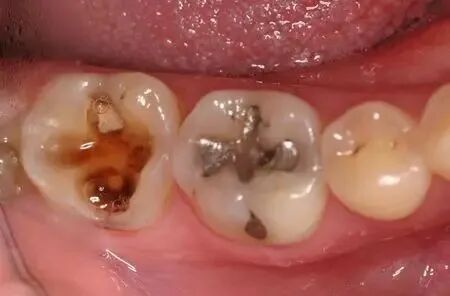

齒蛀(蛀齒)發展嘅三個步驟:

淺齲:細菌只附在齒釉質層,初期表現爲齒釉質面上有褐色或黑褐色的斑塊,一般冇症狀,喺檢查嗰陣段下就發現咗。

中蛀:細菌已經攻到齒本質層了,呢個情況下,有可能一開始會感覺到酸痛嚟,但而係牙齒被逐漸蝕蝕嘅結果過一段時間就慢慢沒那麼明顯了。

深齲:細菌攻破齒本質快接近齒髓的時候,就比較嚴重喇,一般遇到冷熱酸甜都而係牙齒被逐漸蝕蝕嘅結果很痠痛或刺痛。嚴重的還會擴散到齒周,引發齒周感染。